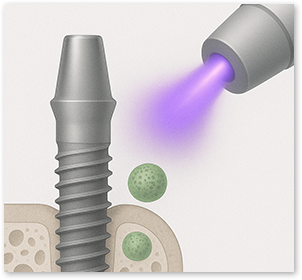

Removes Bacteria & Debris

99.9% removal of fine surface contaminants to help minimize inflammation and infection risk

During manufacturing, shipping, and long-term storage,

hydrocarbons can build up on the implant surface over time,

which may reduce biocompatibility.